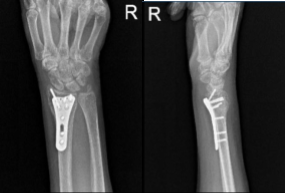

Xray were presented found comminuted impacted volarly angulated and volarly displaced intra-articular fracture of the distal radius. However, do not see any significant joint incongruity or step-off. There is ulnar plus variance. Minimally displaced fracture through the base of the ulna styloid. There is soft tissue swelling and joint effusion.

C-arm images were taken and manipulated to be in the correct position. Finding The plate in appropriate position, fixation of the distal radius performed using locking and nonlocking screws distally and proximally.

After two weeks, the patient checked in with a presented Xray and saw that osseous and metallic elements are in good alignment. Patient is still in splint but not taking any pain medications. In 4th week’s post operation, observed plate fixing the distal radius is again noted with screws holding the plate in good position.

AP and Lateral View of Patient RT 2 weeks Post-operative

AP and Lateral View of patient RT wrist 2 weeks Post-operative